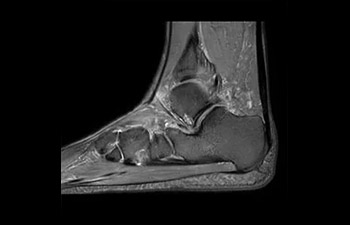

• Es una innovadora técnica de aceleración que no solo permite agilizar las secuencias, sino todo el estudio. • Implementación especial con la que las exploraciones en 2D y 3D pueden llegar a ser hasta un 50% más rápidas con una calidad de imagen prácticamente equivalente.1

• Se puede usar con todos los contrastes y con todas las regiones anatomías.